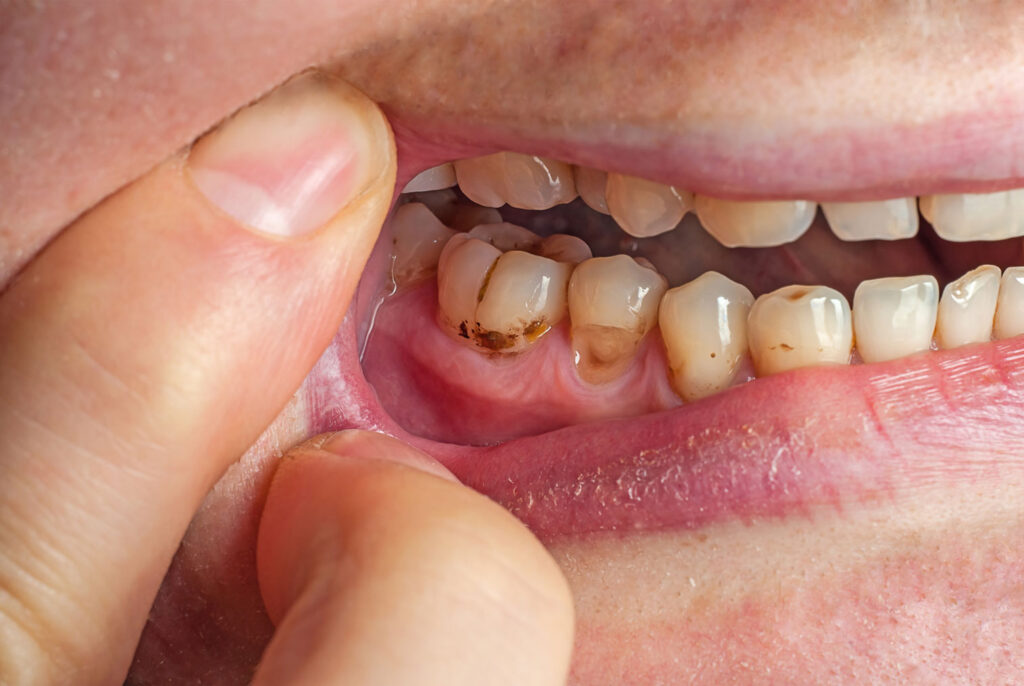

Tooth Decay

The build-up of tartar and plaque causes tooth decay. These deposits eat away at the enamel of the teeth, making them weak and brittle. If the condition gets bad enough, then an infection can develop, causing intense pain, swelling, and redness. Once a tooth reaches this point, it may be necessary to completely remove the tooth and replace it with a dental bridge to avoid further health concerns.